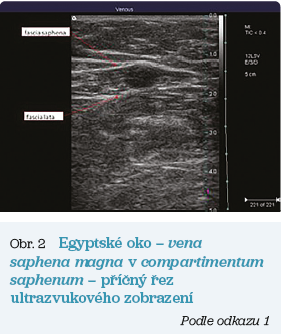

Obr. 2 Egyptské okoNejznámějším znakem VSM v příčném řezu ultrazvukového obrazu je tzv. egyptské oko. Tento charakteristický znak pro uložení kmene VSM ve fasciální duplikatuře fascia saphena vytváří vlastní úzký prostor zvaný safenózní kompartment (compartimentum saphenum) (obr. 2). Toto uložení VSM umožňuje její odlišení od souběžně procházejících podkožních přítoků.